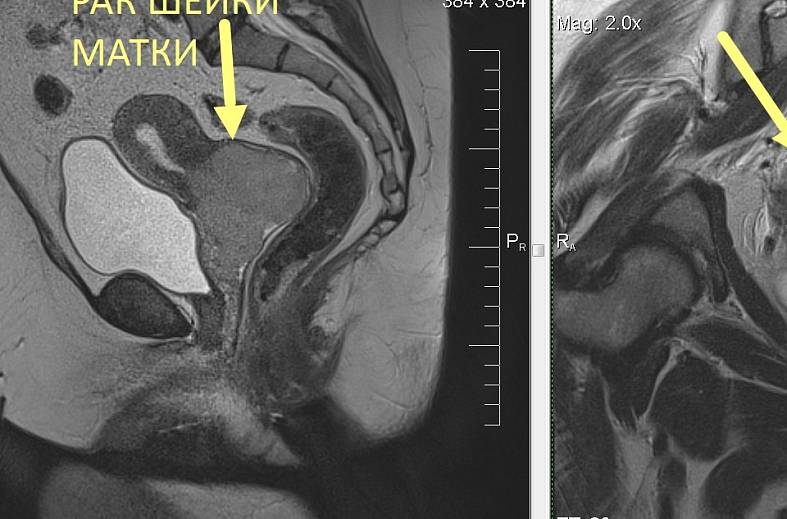

КТ диагностика тубоовариального абсцесса: Подходы и изображения

Раздел: Объективный взгляд